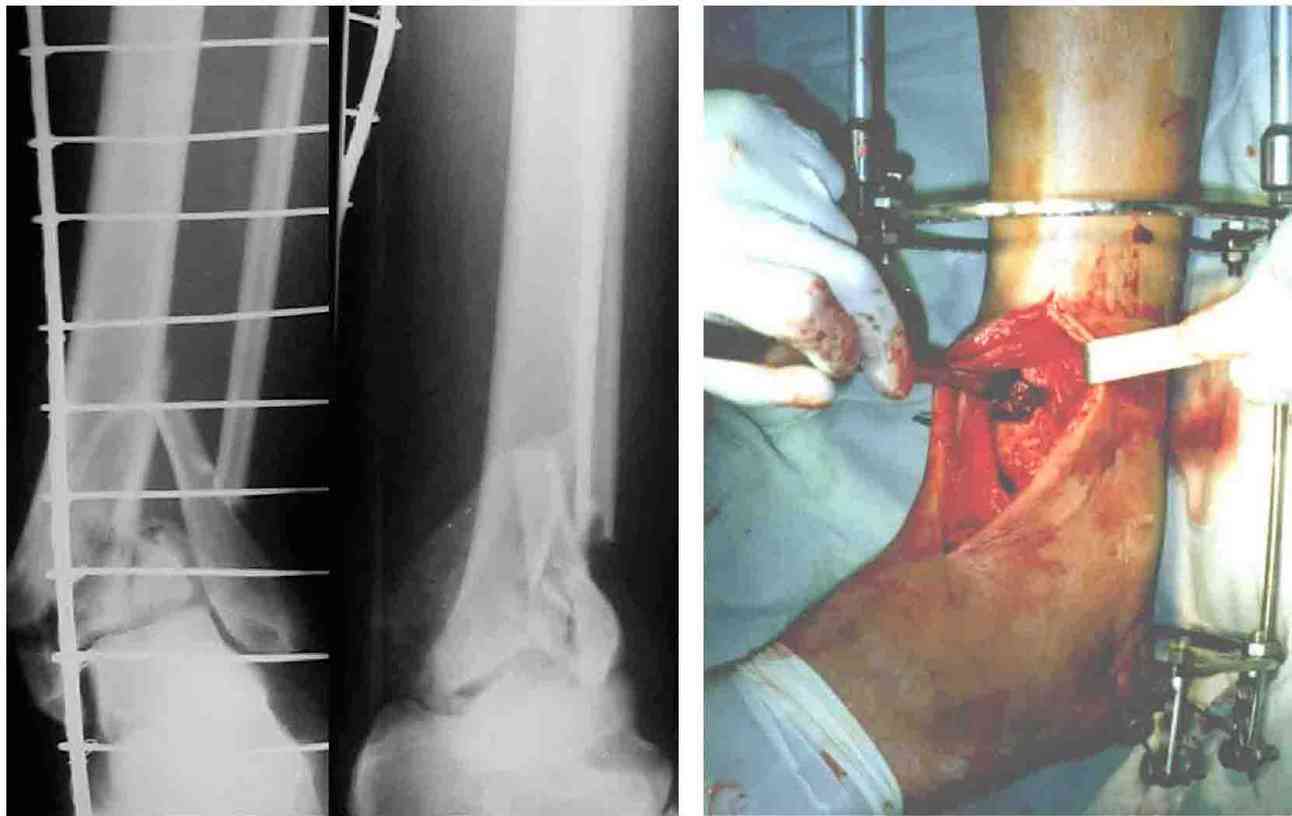

Во вложении - картинки из моей книжки как раз по этой теме

Схемы коррекции различных видов смещения в аппарате

Коррекция длины

Коррекция ротации

Коррекция ширины

В следующих письмах - дополнительные иллюстрации

Открытая репозиция.

Ничто особо не мешает, наоборот - все видно, требования к фиксации не очень высоки - можно просто фиксировать спицей или винтомю Внешний аппарат берет основную нагрузку

Пример -

задний край и диафиз

По поводу конкретного вопрошаемого случая:

1. Скорее всего в аппарате удасться вывести закрыто всё, кроме внутренней лодыжки. Открывайтесь и фиксируйте либо спицей с упором,

либо винтом.

2. ЭОП - очень спорное достижение в таких случаях. Сильные искажения.

Буквально вчера переделывали практически похожий случай. На ЭОПе всё идеально. На пленке - ступенька переднего края. Брали повторно, но уже

пригласили рентгенлаборантку в операционую сделать снимок.

3. Последнее время всё чаще делаем аппарат Илизарова в симбиозе с винтами, которыми фиксируем края (передний и задний), лодыжки и теперь - диафиз.

Позволяет пораньше снять аппарат.

Мы бы фиксировали пластиной м/берцовую кость открыто, на б/берцовую пластину MIPO, при необходимости сустав открыть минимально.

На фото простой суставной, метафиз. оскольчатый с переходом на диафиз перелом, пластина MIPO.

Коллеги подсказали различные варианты фиксации, включая минимальный открытый метод с фиксацией в аппарате Илизарова (Артемьев), а также перкутанный метод (Миронов) пластиной с угловой стабильностью.

Несмотря на различия методик, оба случаи, кстати сделанные на превосходном уровне, заслуживают внимания тем, что первостепенной задачей был поставлено восстановление суставной поверхности.